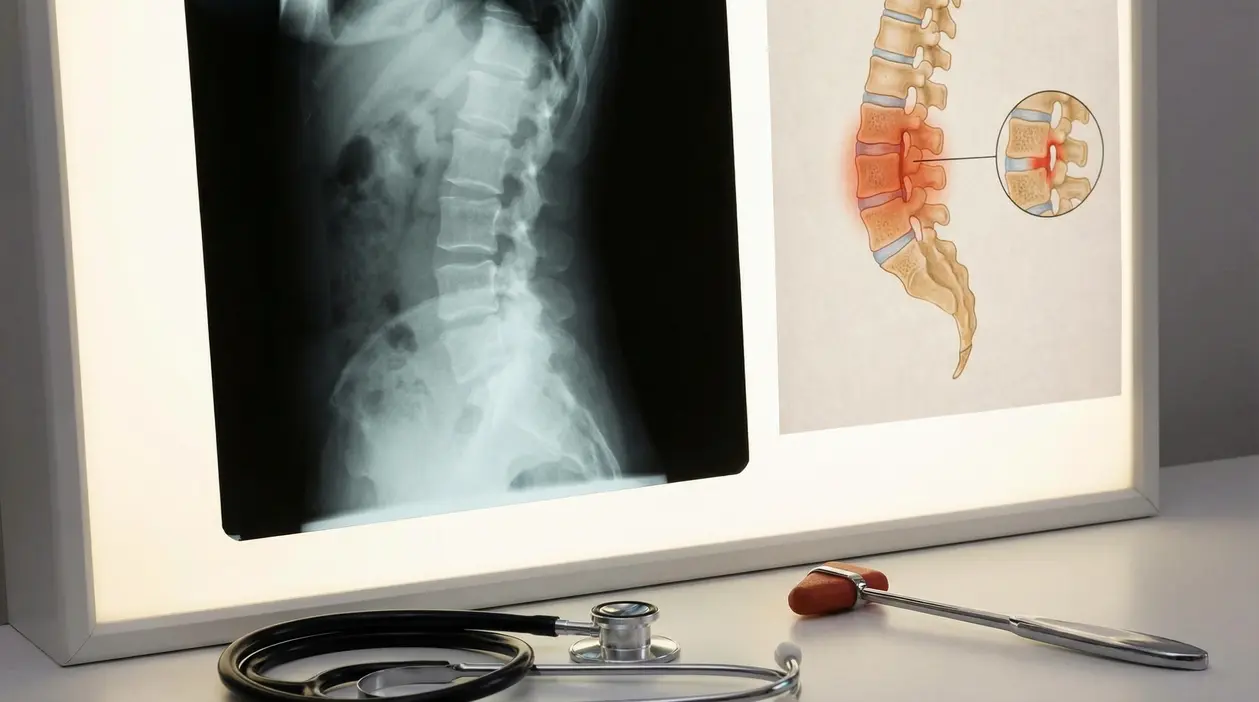

Imaging: radiografia o risonanza?

Qui spesso si gioca la diagnosi precoce.

- Radiografia di sacro-iliache e colonna: utile nelle forme “radiografiche”, quando i segni sono già strutturati.

- RM pelvica o spinale: fondamentale per vedere l’infiammazione precoce, anche quando la radiografia è ancora normale (forme non radiografiche).

Se vuoi un’immagine mentale, pensa alla radiografia come a una foto delle “conseguenze”, e alla risonanza come a una luce che rivela il fuoco mentre brucia.